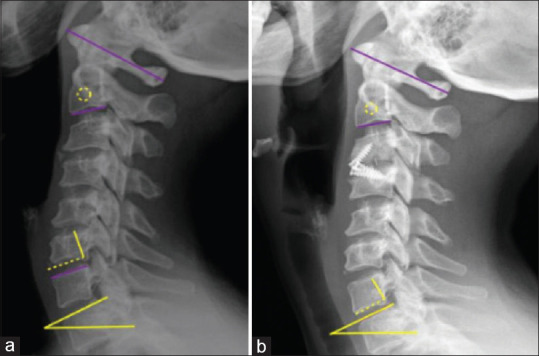

Subjects and methods: We analyzed 63 patients with ACDF with a minimum of 2 years of follow-up. In the imaging evaluation, sagittal balance parameters were included, as well as radiographic parameters that target the development of ASDeg. In addition, discrimination was made between arthrodesis techniques.

Aims: The primary objective of this study is to evaluate the hypotheses that postoperative sagittal imbalance influences the development of adjacent segment degeneration (ASDeg) in patients who have undergone an anterior cervical discectomy with fusion (ACDF).